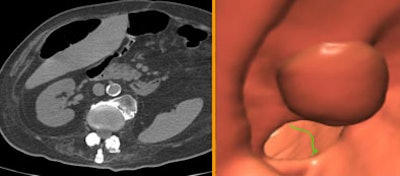

![]() |

| Above and below: Despite suboptimal distension, VC detected two significant polypoid lesions in the sigmoid colon of a 61-year-old paraplegic with fecal occult blood, following unsuccessful colonoscopy. The patient's parents had both died of colon cancer. Digital subtraction was used to detect the fluid-submerged polyps. |

| In a 72-year-old screening patient with severe diverticular disease, the colonoscope had stopped at the sigmoid colon. VC results showed the colon to be free of disease, but detected a very large extracolonic mass, diagnosed as a peritoneal liposarcoma. |